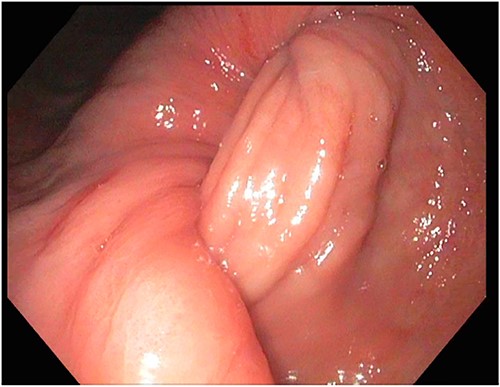

A 72-year-old patient with no past surgical history and a past medical history of developmental delay, hypertension and hyperlipidemia presented to the Emergency Department in mild distress with periumbilical abdominal pain, nausea and intractable vomiting for 1 day. The patient denied any hematemesis, bowel changes, fever, melena or hematochezia. On physical exam, the abdomen was unremarkable, and a computed tomography (CT) scan with contrast of abdomen and pelvis revealed a 5.6 × 5.3 cm heterogeneous mass arising from the body of the stomach extending into pylorus with no evidence of bowel obstruction and liver metastasis (Fig. 1). Subsequently, esophagogastroduodenoscopy (EGD) showed a large, fungating and ulcerated mass and it was reported to involve two-thirds of the luminal circumference in the gastric body (Fig. 2). Cold forceps biopsy showed gastric mucosa with hyperplastic changes, mild chronic active antral gastritis with focal intestinal metaplasia, negative for Helicobacter Pylori and dysplasia. Surgical management was discussed with the family, but they refused any surgical intervention.

A large fungating gastric mass arising from the body of the stomach on endoscopy.